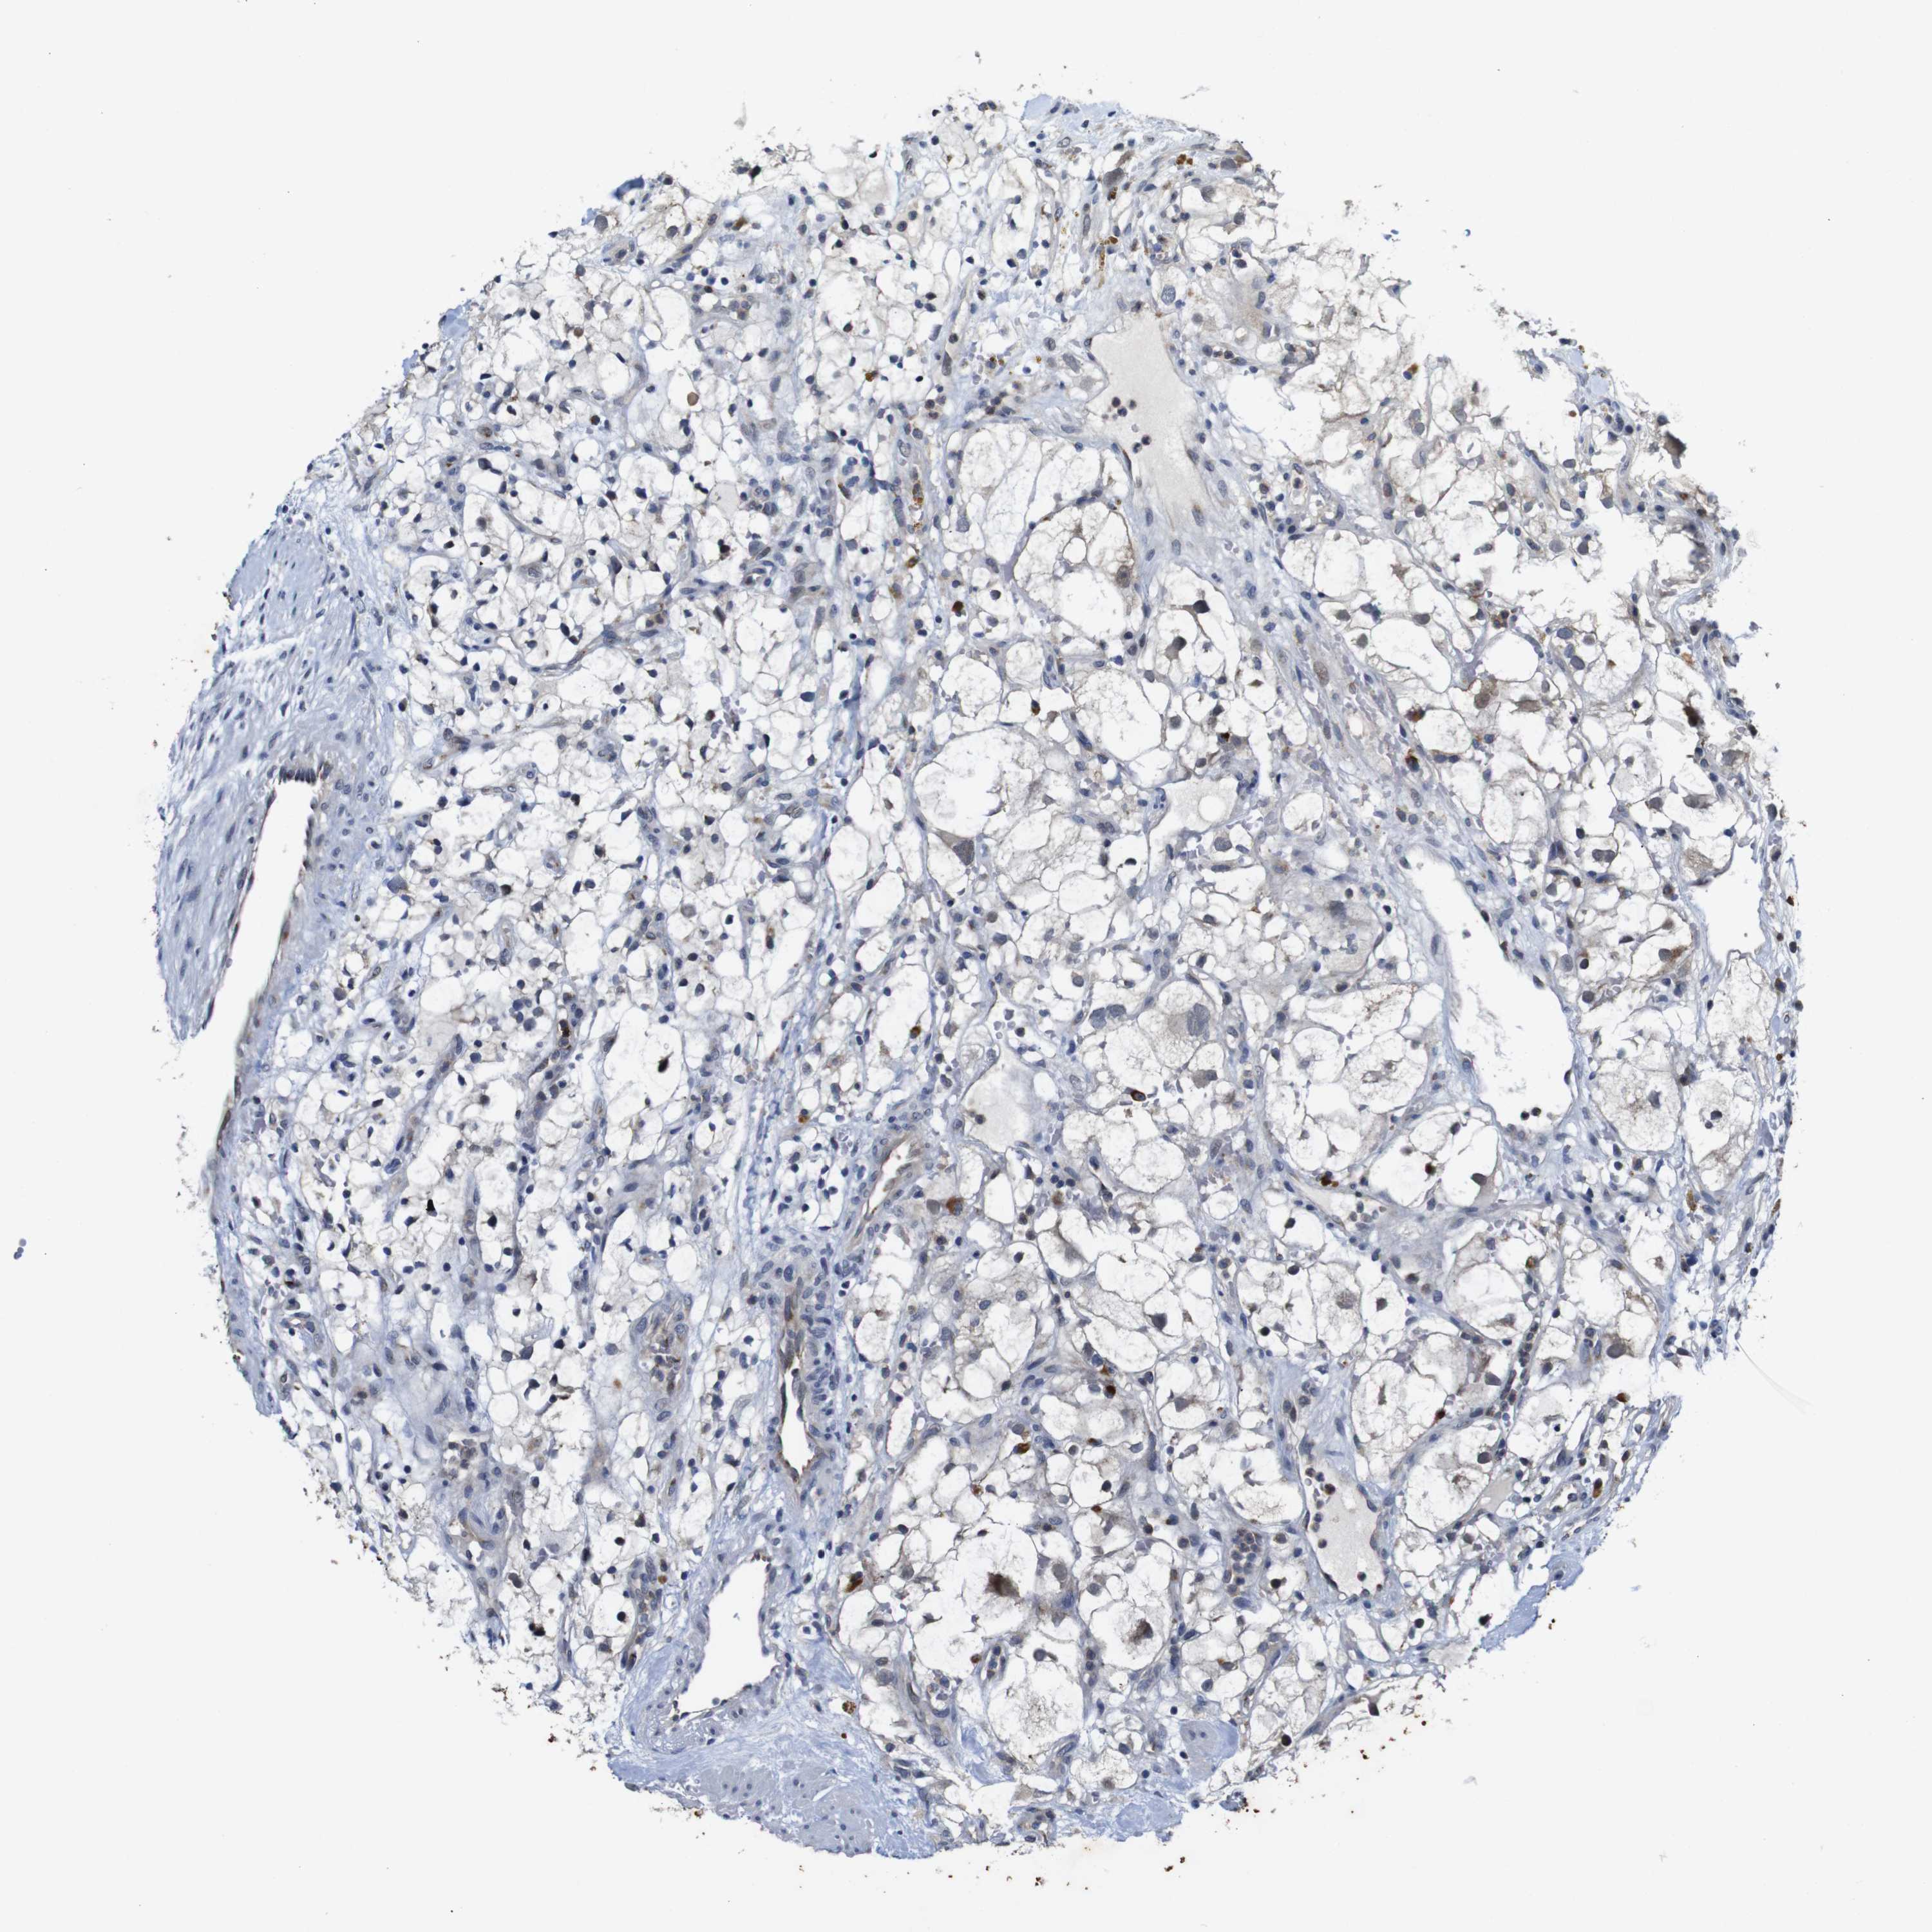

KIDNEY RENAL CLEAR CELL CARCINOMA (VALIDATION) - Interactive survival scatter ploti

FURIN is not prognostic in Kidney Renal Clear Cell Carcinoma (validation)

Best expression cut offi

: 45.14

Average pTPM 43.6

Number of samples 100